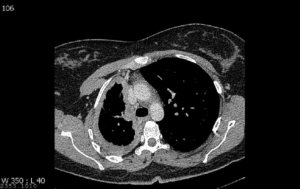

A 76-year-old woman has progressive breathlessness with right-sided pleuritic chest pain and weight loss over 6 months. She is a retired mechanic and has a 25 pack-year smoking history. Investigations: Chest X-ray: marked volume loss in right hemithorax CT scan of the chest: see image

The symptoms and imaging findings described in the scenario are consistent with malignant pleural mesothelioma. The CT image shows marked volume loss in the right lung and the right lung is encased with tumour. The patient may have been exposed to asbestos at her job as a mechanic (brake pads, etc.). Chronic hypersensitivity pneumonitis and asbestosis have changes in the lung fields, not the pleura. The changes are usually bilateral and crackles are heard at the area of abnormality. This patient’s history would fit with lung cancer, and she does have risk factors for lung cancer (smoking and asbestos exposure) but chest pain is more common with mesothelioma, and the CT scan appearances are classical of mesothelioma as the thickening is of the pleura. TB can mimic anything but it is less likely in this case and there is no fever.